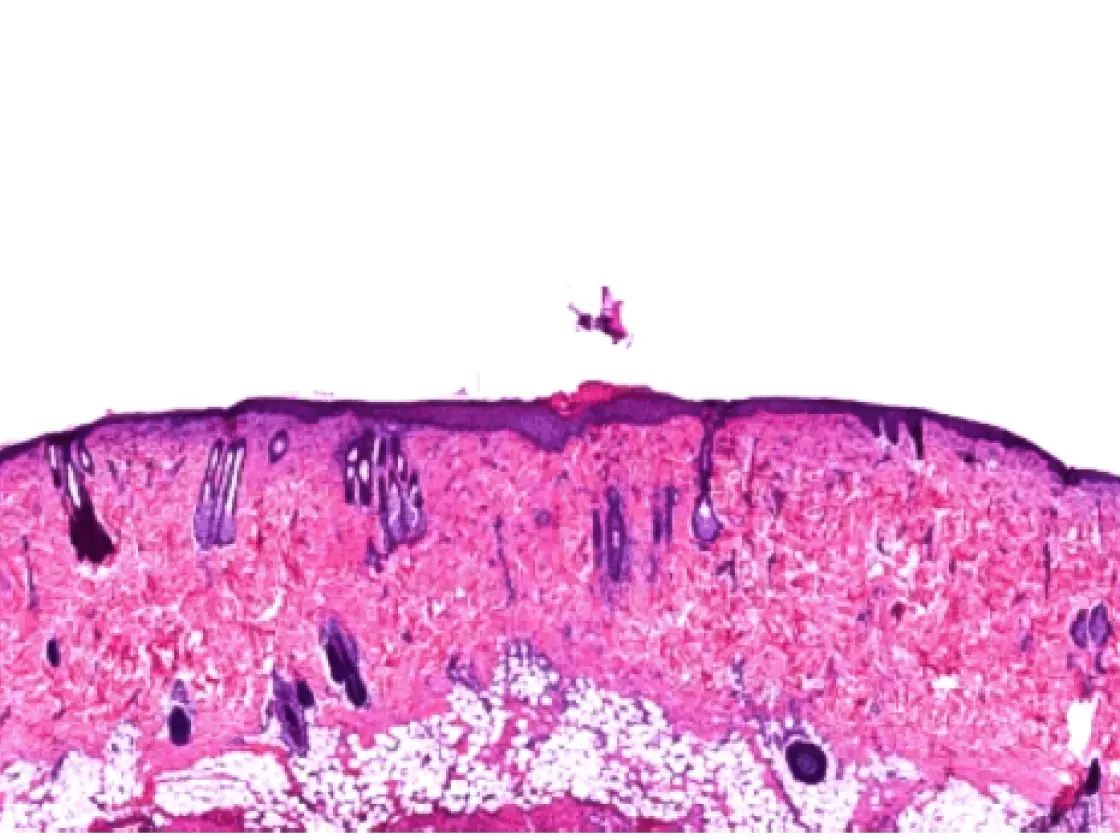

A comparison of the healing process of lesions in albino rats created by different technologies showed proven benefits of the 4 MHz radiofrequency technology in terms of wound healing. Using the impedancecontrolled CURIS© 4 MHz radiofrequency generator turned out to be more targeted and precise compared to conventional high frequency, preserving the basal membrane as well as the deep layers of the epithelium, thus causing less profound wounds.6 The histological assessment also showed that wound healing using the CURIS© 4 MHz radiofrequency generator is faster compared to conventional high frequency. Radiofrequency induced wounds show complete epithelialization after seven days in contrast to the lesions produced by high frequency which show abundant inflammation associated with focal suppurations (see fig. 2).

Histological aspects on day seven: comparing radiofrequency and conventional high frequency

Fig. 2